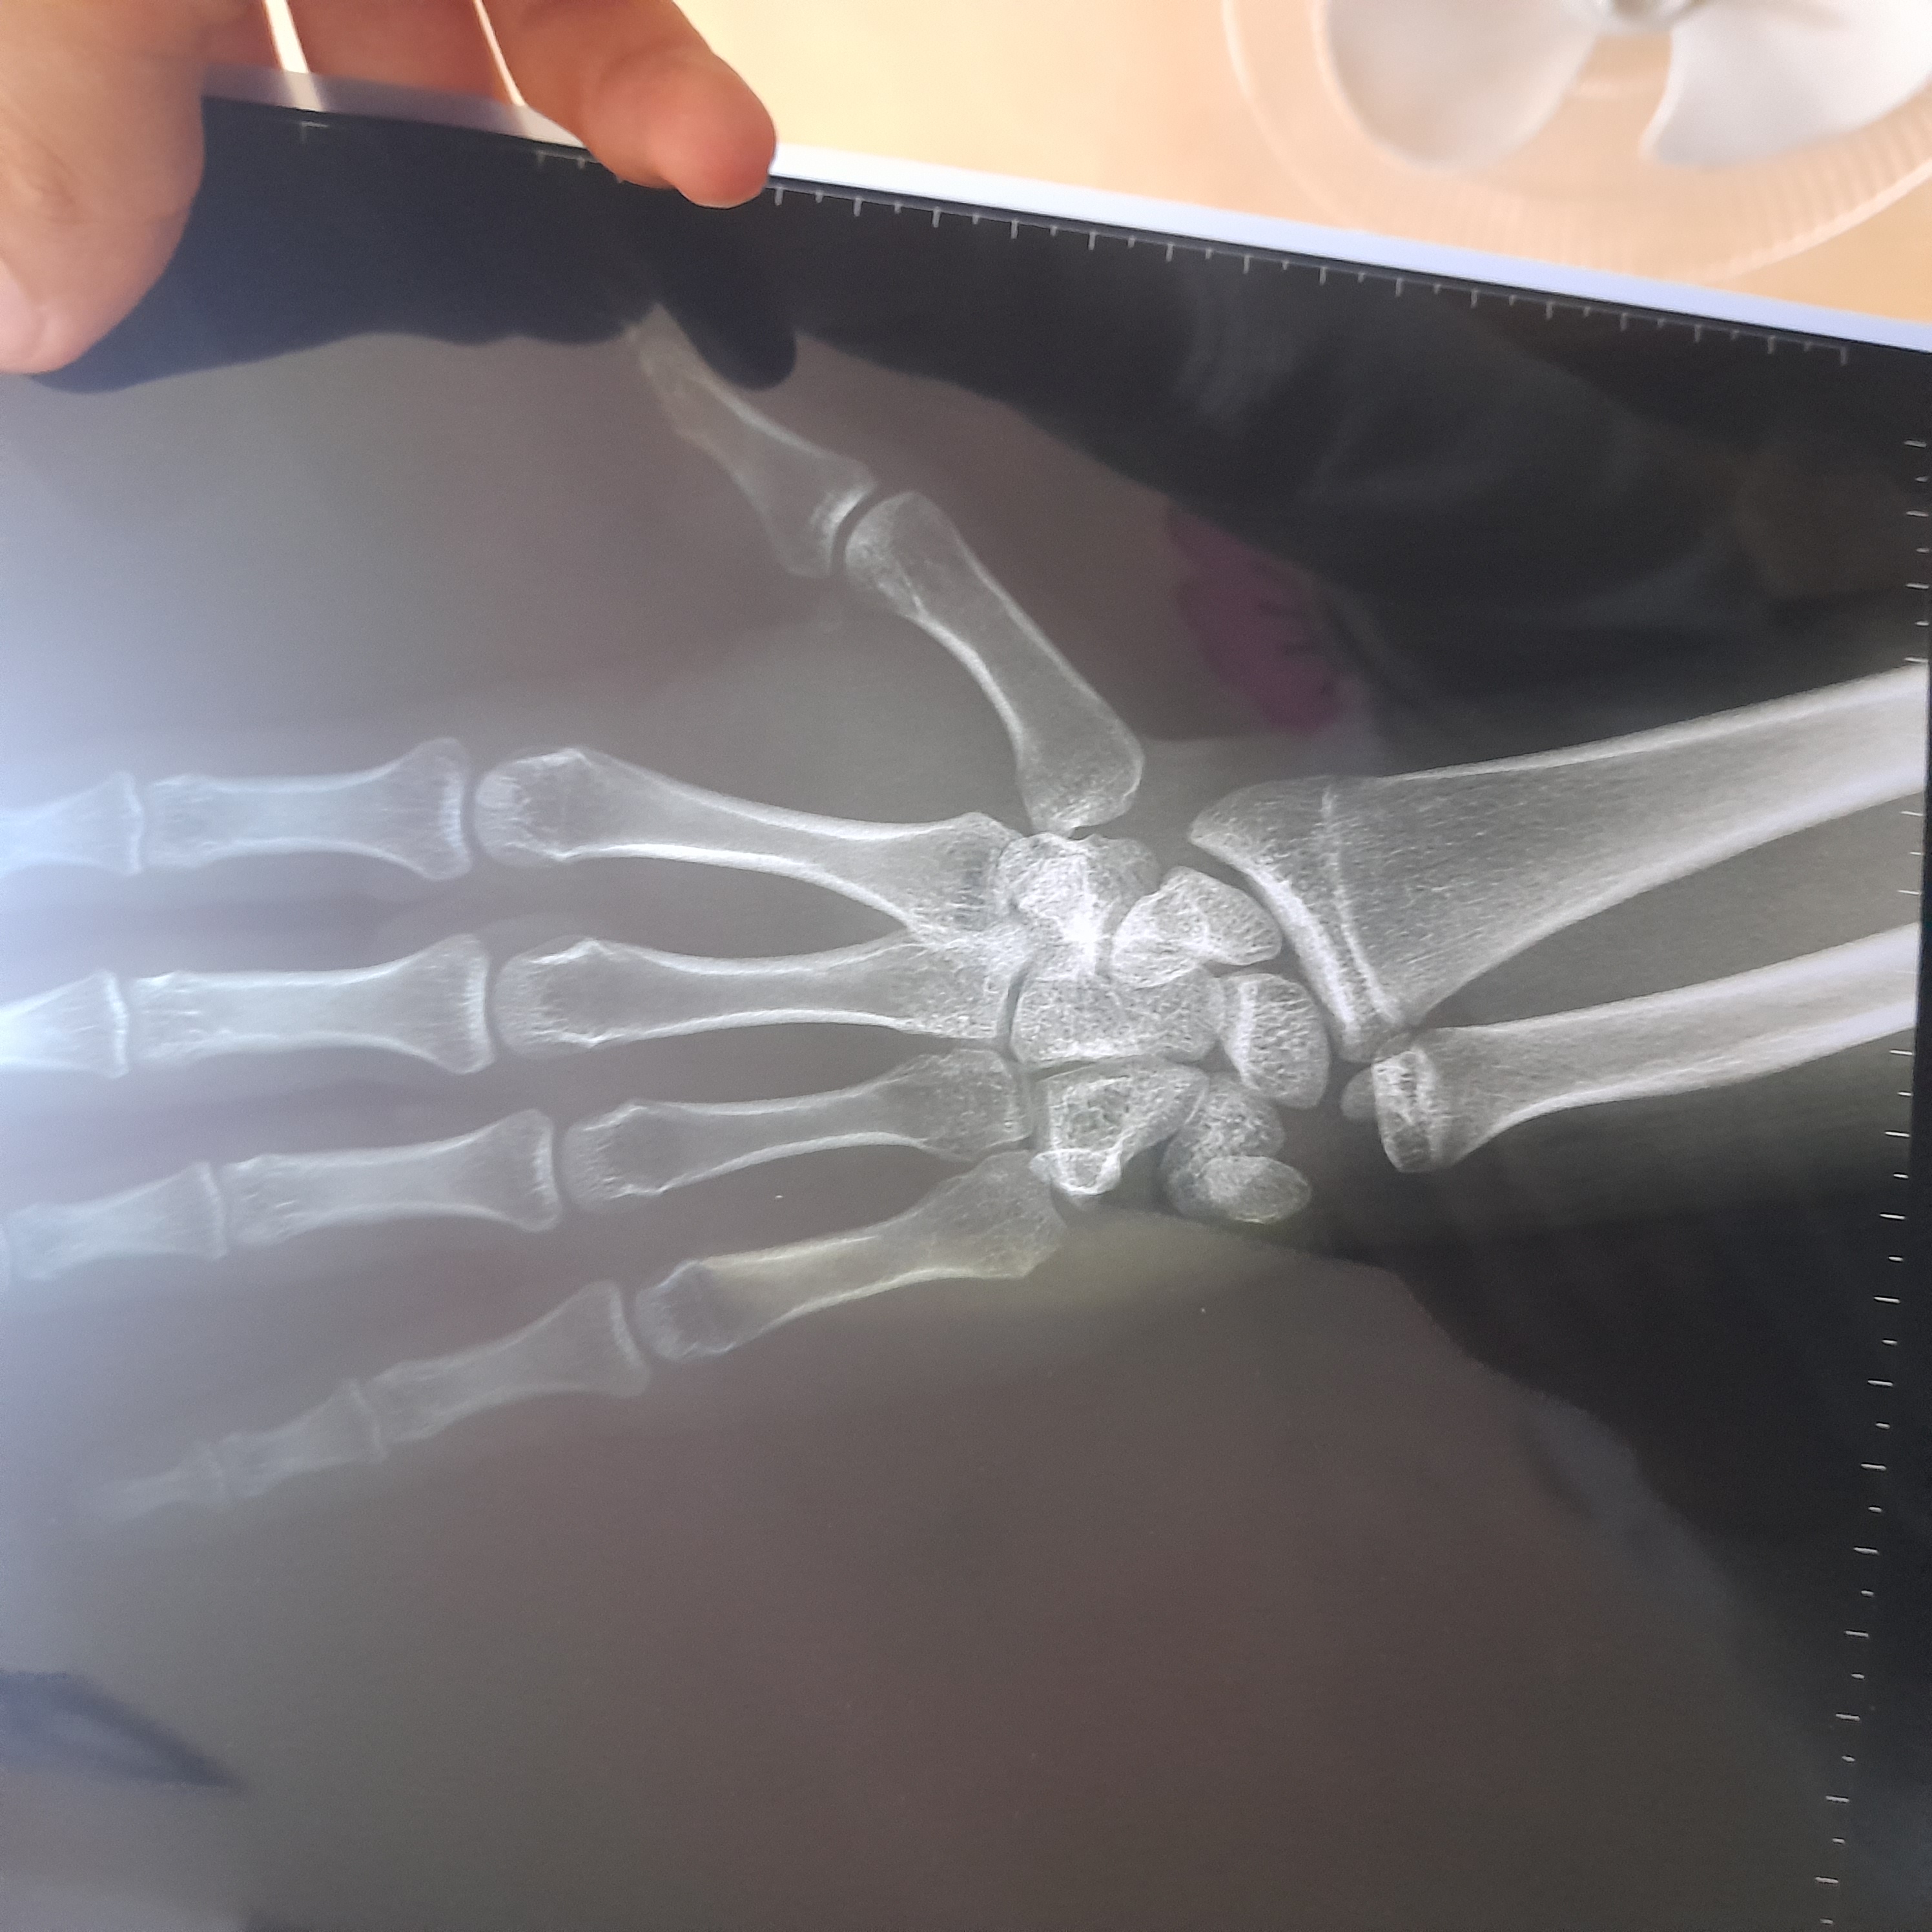

icon 131

عمري 15 و 10 اشهر و هذه اشعة ليدي اليسرى و اريد معرفة هل الصفائح مغلقة او مفتوحة و اريد ايضا معرفة كم المدة الذي من الممكن ان تبقة مفتوحة و كم الزيادة الذي استطيع الحصول عليها من الطول

IMG-20251128-WA0000 ٢٠٢٥١١١٦_٢٠٠٣٣٣